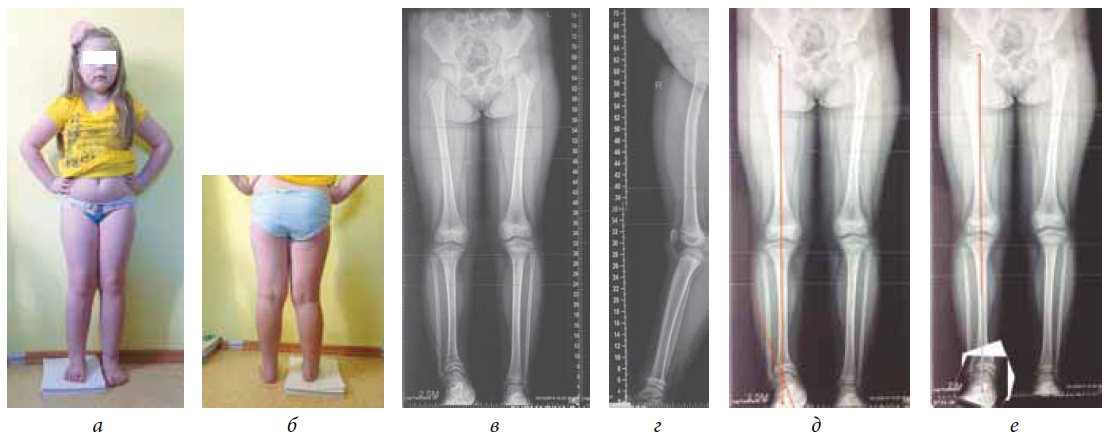

Раздел: Снимки-откровения